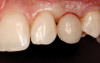

(57.) The provisional restoration was delivered and tightened to 15 Ncm while applying counter torque. Note that there is no pressure on the surrounding tissues and that the gingival embrasures were left open to allow for maximum incisal migration of the gingiva and papillae. The palatal and incisal surfaces were evaluated and modified to ensure that there was no contact throughout the excursive range.

Figure 57